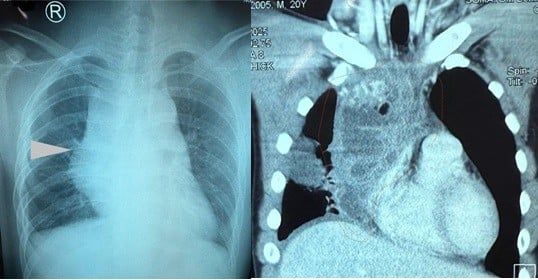

Người bệnh sinh năm 2005, là sinh viên. Bản thân người khỏe mạnh chơi được nhiều mô thể thao: đá banh, cầu lông, bóng bàn, bơi lội. Khoảng 2 tuần trước khi nhập viện người bệnh cảm thấy đau vùng lưng ngay xương vai phải lan ra trước ngực, cảm giác căng tức mệt thở khó được chuyển đến bệnh viện Nhân 115 chụp hình phổi kiểm tra phát hiện u trong lồng ngực với bóng trung thất to. Sau đó được chụp CT ngực có cản quang phát hiện khối u rất to trong lồng ngực chèn ép vào tim, phổi và tĩnh mạch chủ. Kích thước khối U khoảng 10cm X 7cm X 7cm bờ đa cung giới hạn không rõ, đậm độ thấp, thành dày tăng bắt thuốc cản quang, tụ dịch khu trú nhĩ phải, xẹp thụ động thùy dưới phổi (P).

U quái trưởng thành ở trung thất thường lành tính. U quái lành tính ở trung thất được thấy với tần suất như nhau ở nữ và nam. U quái thường phát triển chậm, bệnh nhân thường không có triệu chứng và khối u được phát hiện tình cờ trên phim chụp X-quang tim phổi thẳng. Hầu hết các triệu chứng đều liên quan đến chèn ép các cấu trúc lân cận như đau ngực, khó thở, ho hoặc nhiễm trùng phổi. Chụp X-quang ngực thường cho thấy khối u trung thất trước. CT ngực thường là phương thức chẩn đoán hình ảnh được lựa chọn để chẩn đoán u quái trung thất, giúp xác định vị trí và các cấu trúc lân cận của khối u cũng như các thành phần bên trong gồm mô mềm, mỡ và canxi hóa. Siêu âm tim thường cho thấy khối u ngoài màng ngoài tim và chèn ép các cấu trúc mạch máu lớn. MRI cũng được sử dụng để đánh giá u quái trung thất. MRI cho thấy khối u có cường độ tín hiệu không đồng nhất, nhạy trong việc mô tả sự thâm nhiễm của các cấu trúc lân cận.